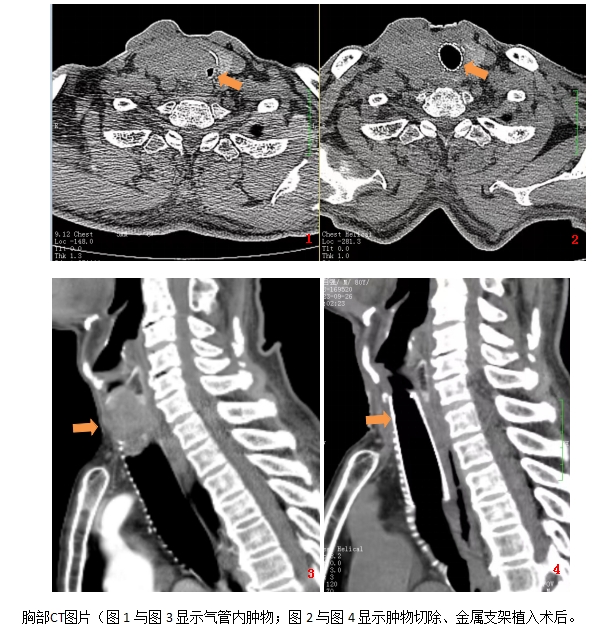

家住长沙80岁李先生,因重度呼吸困难就诊于呼吸五病区经相关检查明确为甲状腺癌长入气管,使气管只剩下一条狭窄的缝隙,引起严重呼吸困难。因已经无法手术,所以支气管镜下切除气管肿物并植入金属支架是缓解病情的首选治疗。但由于患者肿物离声门不到1cm,气管几乎完全堵塞,支气管软镜治疗风险大,且放置的金属支架极易移位。

呼吸五病区副主任罗曼主任医师及重症介入组陈云荣主任医师术前详细讨论手术方案,做好充分准备的前提下9月25日陈云荣介入团队给患者在支气管软镜下进行了介入治疗。手术前,医护团队通过预先放置吸痰管接氧气保证氧合,并在切除气管内大部分肿瘤、植入金属覆膜支架后,用手术缝线把支架固定在气壁上。手术十分顺利,术后患者呼吸困难显著缓解,复查胸部CT支架位置良好无移位,患者及家属感激不尽。